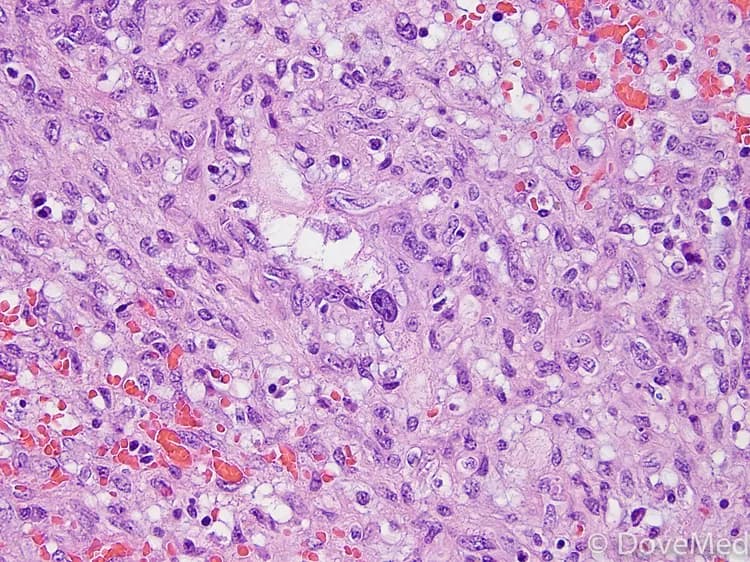

Angiosarcoma of Soft Tissue is an infrequent, aggressive, but often rapidly developing tumor, without signs and symptoms in the early stages. The tumor arises from the vascular linings, which involve the blood vessels. Test your knowledge of this disorder by taking our quiz!